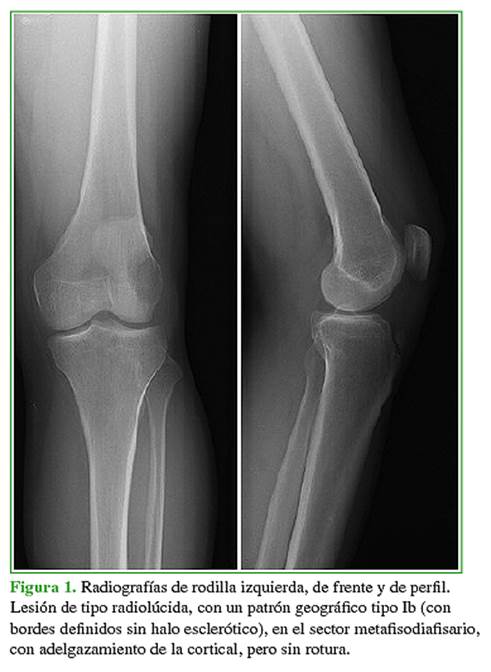

En las radiografías de rodilla izquierda, de frente y de perfil, se visualiza una lesión radiolúcida, con un patrón de tipo geográfico, de bordes definidos, pero sin halo esclerótico, en íntimo contacto con la cortical externa en el sector metafisodiafisario distal del fémur (Figura 1).

Hombre de 36 años que consulta por gonalgia izquierda luego de la actividad física, sin un antecedente de trauma. No refiere dolor durante las maniobras dinámicas ni palpatorias. Se solicitan radiografías de rodilla izquierda, de frente y de perfil, y se completa la evaluación con una resonancia magnética sin medio de contraste.